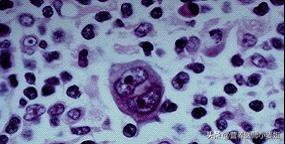

人間のがん細胞は、もともとは正常な細胞であり、遵法精神に富む「善人」であるが、さまざまながん原因因子の作用により、「悪人」へと疎外されてしまった。 本来、私たちの身体の免疫システムは、人間社会の監視器官のように、これらの「悪人」を的確に狙撃できる強力な免疫監視の役割を担っているが、一部のがん細胞は非常に狡猾であり、さまざまなメカニズムによって、免疫システムの監視と排除からうまく逃れている。本来、私たちの身体の免疫システムは、人間社会における監視器官のように、これらの「悪人」を的確に狙撃できる強力な免疫監視の役割を担っているが、一部のガン細胞は非常に狡猾で、免疫脱走と呼ばれる様々なメカニズムによって、免疫システムの監視・駆除からうまく逃れ、牢獄からの脱獄に成功し、その結果、遺伝子レベルから生体の制御が効かなくなり、無秩序な成長・繁殖を引き起こし、ガンの発生を誘発する。無秩序な増殖と生殖の過程で、血管新生、クローン性の異常増殖を誘発し、正常な細胞の栄養を略奪し、正常な組織を破壊し、"殺人・放火魔 "へと変貌を遂げ、最終的に患者の生命を危険にさらしたのである。善人」と「ヤクザ」の中間段階が前がんである。下の写真はがん細胞である。